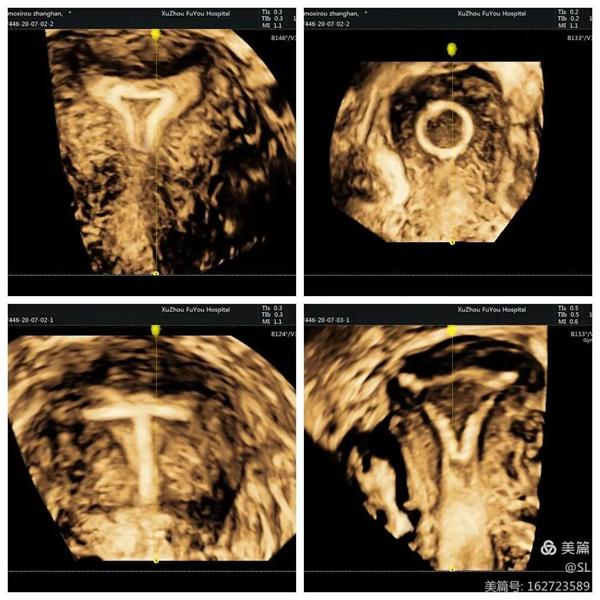

据张丽主任介绍,经阴道三维彩超是使用容积探头对宫腔内的病变及盆腔进行三维成像,可多模式重建成像,全方位、多视角完整、立体显示宫腔内部结构和空间位置关系,直观清晰的立体成像对妇科疾病的诊断更加准确,在妇科检查中得到广泛应用。

先天性子宫畸形是妇科的常见疾病,也是女性不孕不育、习惯性流产、胎儿宫内发育迟缓等疾病的主要原因之一。经阴道三维彩超在评估子宫病变等方面,提供了更丰富的影像信息。这种超声技术不仅能够更好的观察子宫外形轮廓及宫腔内膜的形态,还能清晰观察患者宫腔内的可疑部位和周围组织,帮助医生更准确的分析判断病情。

张丽主任提到,经阴道三维超声是在二维超声基础上技术升级的检查手段。二维超声是断层扫查,很难显示冠状切面,三维超声可以立体实时、从多个面来观察,提供比二维超声更丰富的信息量,因此医生根据三维彩超来诊断,结果会更加准确。

3、精确定位节育器

节育器是放置在女性子宫腔内的避孕装置,是女性避孕的常用方式之一。但有的患者放置节育器后,会出现一些不良反应,这时往往需要知道节育器的情况。

张丽主任提到,有一位外地患者,因为节育器偏移发生下腹部疼痛,当地卫生院找不准位置取环失败后,连夜转诊到徐州市妇幼保健院。超声科医生通过三维彩超精准定位,确定了节育器偏移到了子宫肌层,最终顺利取出。

三维彩超的立体成像、图像切割、图像旋转及高平面图像分析功能,能直观、立体显示宫腔的形态结构及其与周边邻近组织的立体关系。因此,清晰显示节育器位置及形状,便于医生操作,也可以大大减少患者的痛苦。